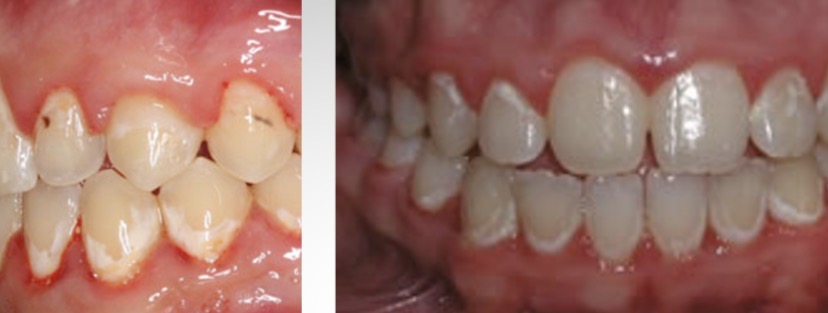

What is this condition?

Tetracycline stain

-Endogenous/intrinsic stain